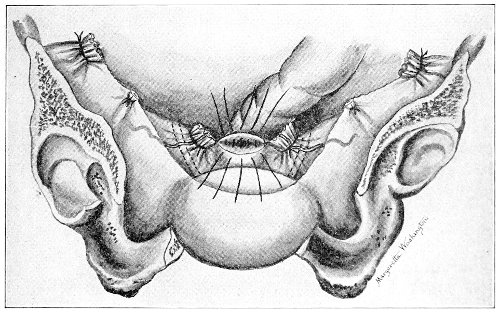

An accurate knowledge of the anatomy and mechanism of the female perineum is essential to an understanding of the nature and treatment of injuries to this structure. The anatomical structures lying between the anus behind and the symphysis pubis in front are those that most directly interest the gynecologist. Proceeding from 57 below upward, we find the following structures lying in superimposed planes: the skin, the superficial fascia, the deep layer of the superficial fascia, the transversus perinæi and the sphincter vaginæ muscles, the anterior layer of the triangular ligament, the posterior layer of the triangular ligament, the levator ani muscle (Fig. 19).

Fig. 18, A.—Superficial structures of the female perineum (Weisse).

Fig. 19.—Dissection of female perineum: on the left side the perineal muscles are exposed by the reflection of the perineal fascia; on the right side the muscles and the superficial layer of the triangular ligament have been removed, thereby exposing the deep layer of the ligament. S. V., Sphincter vaginæ muscle.

The vagina passes through these structures. They surround and support the ostium vaginæ as the fascia and muscles surround and support the opening of the rectum or the anus. The muscles and fasciæ are attached in the median line between the anus and the vagina, and therefore this part of the body, which is called the perineum, is supported or maintained in its 58 proper position by these various structures. The transversus perinæi arises from the ramus of the ischium and is inserted in the perineum. The bulbo-cavernosus, or sphincter vaginæ, arises in the perineum and is inserted in and about the clitoris. The inner fibers of the levator ani arise from the symphysis pubis and are inserted in the perineum and the lower part of the vagina (Fig. 20). When these muscles contract, their action, therefore, is to draw the perineum upward and forward. At the same time the anus is drawn upward and forward, and so also is the posterior margin of the ostium vaginæ and the lower portion of the posterior vaginal wall.

Fig. 20.—Dissection of female perineum, showing the deeper structures after removal of the levator and sphincter ani muscles.

The vagina has no circular sphincter like the anus, but 59 the vaginal month is kept closed by the action of the transversus perinæi, sphincter vaginæ, and levator ani muscles, which draw the perineum forward, and thus keep the posterior vaginal wall in apposition with the anterior wall.

Fig. 21.—Muscular floor of the pelvis seen from above.

This sling of muscles and fascia, which surrounds and supports the opening of the vagina, may readily be felt in the nulliparous woman by introducing the finger in the vagina and pressing backward and outward toward the ischio-rectal fossa. We then feel plainly, immediately within the ostium vaginæ, a firm resisting band of tissue, apparently about half an inch broad, embracing the posterior portion of the lower vagina. This band is formed by the inner edges of the various muscles and planes of fascia that have been described.

Fig. 22.—Sagittal section showing relations of the several layers of fascia within the pelvic floor (Dickinson).

The vagina extends, as a transverse slit in the pelvic floor, upward and backward, approximately in the direction 60 of a line drawn from the ostium vaginæ to the fifth sacral vertebra. It is approximately parallel with the conjugate of the brim, so that when the woman is erect the long axis of the vagina is inclined at an angle of 60° to the horizon. The vagina is not a vertical open tube: it is a slit in the pelvic floor, in health always closed by the accurate apposition of the anterior and posterior walls (Fig. 21). The anterior vaginal wall is about 2½ inches long in a vertical mesial line. The posterior vaginal wall is about 3½ inches long. The vaginal walls are triangular in shape, being broader above than below. The shape of the normal vagina at the pelvic outlet is shown by Fig. 23. The section here shows the vaginal 61 slit of the shape of the letter H. The portions of the slit extending backward and somewhat outward are called the vaginal sulci or furrows. They are directions of diminished resistance in which tears are liable to occur.

Fig. 23.—Section illustrating the characteristic form of the vaginal cleft (Henle): Ua, urethra; Va, vagina; L, levator ani; R, rectum.] 62